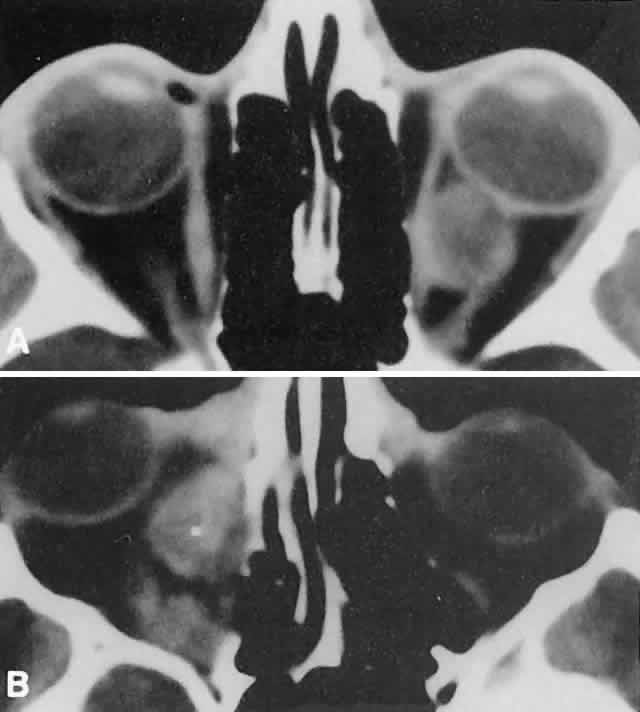

Orbital myositis may represent a greater proportion of cases of IIPT in childhood than in adulthood, and involvement of multiple extraocular muscles may occur more frequently in children than inadults. In orbital myositis, early diplopia and increased discomfort with attempted eye movement are typical symptoms. CT may show enlargement of one or more extraocular muscles in one or both orbits (Figs. 21 and 22). When a single muscle is involved, the specter of a primary or metastatic neoplasm within the muscle may be raised. However, external inflammatory signs, considerable pain and limited motility, and an explosive onset of symptoms within 24 hours all suggest orbital myositis. The uniform enlargement of the muscle, including its tendinous insertion (see Fig. 22), also helps distinguish the process from a neoplasm, which might be expected to produce a more focal, globular expansion. Echography may support the diagnosis of inflammation by showing edema in the episcleral space as a relative sonolucency between the scleral and orbital fat echoes (Fig. 23). Its CT counterpart is an increase in the radiodensity and thickness of the ocular tunica.

Fig. 21. A. This 16-year-old boy had acute onset of bilateral proptosis, pain, diplopia, chemosis, and conjunctival injection. B. Bilateral enlargement of the superior and medial rectus and inferior oblique muscles. Other sections showed similar involvement of other extraocular muscles.

Fig. 22. The uniform enlargement of the left medial rectus muscle, including its tendinous insertion, is characteristic of orbital myositis.